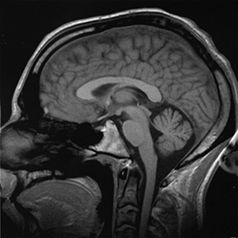

وتمكن تقنيتان جديدتان مأمونتان هما: التصوير المقطعي المغناطيسي بابتعاث البوزيترونات والتصوير بالرنين المغنطيسي الوظيفي، العلماء من دراسة الدماغ السليم أثناء عمله. ولاتتطلب هاتان التقنيتان اتصالاً مباشرًا بالدماغ، ولكنهما ينتجان صورًا شبيهة بصور الأشعة السينية، والتي توضح أي أجزاء الدماغ يعمل أثناء أداء الشخص نشاطًا ذهنيًا أو بدنيًا، حيث يوضح التصوير المقطعي بابتعاث البوزيترونات أجزاء الدماغ الأكثر استهلاكًا للجلوكوز، بينما يوضح التصوير بالرنين المغنطيسي الوظيفي، الأجزاء التي يشير فيها استهلاك معدلات عالية من الأكسجين إلى نشاط الجزء.

وقد مكنت الأجهزة والتقنيات الحديثة الأطباء من تشخيص اضطرابات الدماغ مبكرًا، وبشكل أكثر دقة مما كان في الماضي. فالجهاز المسمى مخطاط كهربائية الدماغ، مثلاً، يقيس أنماط النشاط الكهربائي الناتج عن الدماغ، وقد تشير الفروق عن الأنماط الطبيعية لمخطاط كهربائية القلب إلى حدوث تلف بالدماغ، وقد يساعد في تحديد منطقة الإصابة. ويمكن لمخطاط كهربائية القلب المدعوم بالحاسوب، رصد وتنظيم كميات كبيرة من البيانات الكهربائية، كما يمكنه أيضًا قياس استجابات الدماغ لبعض المؤثرات البصرية والسمعية واللمسية. ويستطيع العلماء تشخيص الاضطرابات بمقارنة هذه الاستجابات مع متوسط النتائج المأخوذة من عدد كبير من الناس. وتنطوي تقنية أخرى تسمى التصوير المقطعي الحاسوبي على تصوير الدماغ بالتفصيل من عدة زوايا باستخدام الأشعة السينية. ويقوم الحاسوب بتحليل بيانات الأشعة السينية، ويرسم صورة مقطعية للدماغ على شاشة تلفازية. وتستخدم تقنية أخرى تسمى التصوير بالرنين المغنطيسي المجالات المغنطيسية والموجات الراديوية لإنتاج صور عن تركيب الدماغ.